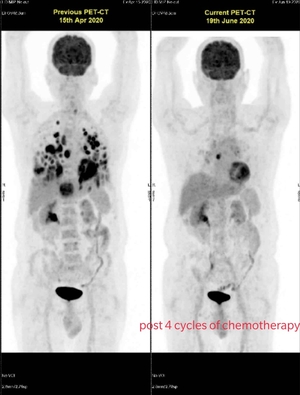

Neoadjuvant chemo in breast cancer by Dr. Rahul Kulkarni

Neo- Adjuvant Chemotherapy - Dr. Rahul Kulkarni

What is Neo-Adjuvant? Neoadjuvant Chemotherapy means the use of Chemotherapy/targeted therapy before definitive local treatments like Surgery or Ra...